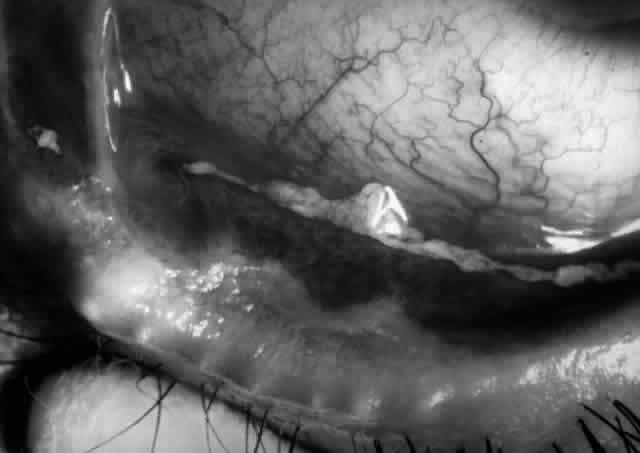

Clinically, the ocular disease in cicatricial pemphigoid (OCP) may present unilaterally in the form of a chronic, recurrent catarrhal conjunctivitis, but it eventually becomes bilateral. Subepithelial fibrosis is characteristic of stage 1 of OCP (Fig. 7). Stage 2 shows fornix foreshortening (Fig. 8), and symblepharon formation is the hallmark of stage 3 (Fig. 9). Stage 4, end-stage disease, is characterized by ankyloblepharon and surface keratinization (Fig. 10). Obstruction of the lacrimal ductules and meibomian gland ducts eventually produces an unstable tear film and progressive sicca syndrome, but it is to be emphasized that OCP is not a dry-eye syndrome until late in the disease course.20 Trichiasis and entropion occur because of the subepithelial fibrosis, with eventual keratopathy, corneal neovascularization, and corneal ulceration and scarring.20

Fig. 10. Stage 4 cicatricial pemphigoid. Progressive shrinkage of the conjunctiva resulted in extreme trichiasis and distichiasis and keratopathy, with compromise of meibomian ductules and lacrimal ductules and the production of a totally dry eye.